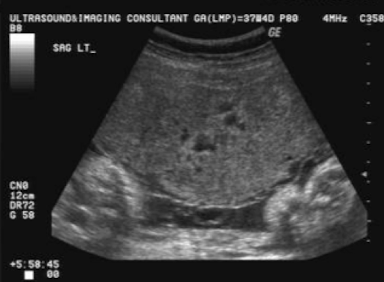

SONO: placenta

homogeneous

pebble-gray—mildly more echogenic compared to uterine wall

may be more echogenic in 1st trimester

smooth borders

highly vascular structure

rim of myometrium outside placenta should be noted

prominent maternal vessels may be seen posterior to placenta (anechoic tubes)

placental lakes may also be seen in placenta